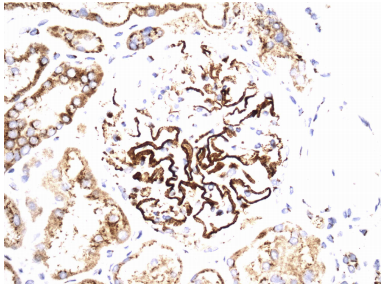

免疫荧光显示IgG(图1b)和κ和λ轻链的3+颗粒节段性至全局性肾小球毛细血管壁染色,伴随着类似分布的2+IgM、1+C3和微量C1。此外,还有局灶性颗粒状TBM沉积物,其IgG、κ和λ染色为1+(图1c)。未观察到系膜、内皮下或动脉血管壁染色。超微结构检查证实存在节段性至全局性上皮下电子致密沉积物,这些沉积物由肾小球基底膜尖峰分隔(图1d),其中一些沉积物发生部分吸收。足细胞表现出70%的足突消失。未发现内皮下或系膜电子致密沉积物、有组织的亚结构或内皮管网状包涵体。

PLA2R的免疫荧光(冷冻切片)呈阴性。在福尔马林固定的石蜡包埋组织上进行NELL1的免疫组织化学染色,突出显示节段性至全局性上皮下沉积(图2a),但在TBM中不存在。TBM中的抗LRP-2免疫荧光染色也呈阴性。

图2. 神经表皮生长因子样1的免疫过氧化物酶染色显示,在上皮下沉积物的分布中,肾小球毛细血管壁呈不完全阳性(原始放大倍数×400),沿肾小管基底膜没有明显的阳性特征